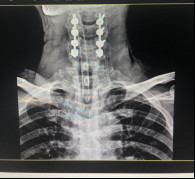

(術前拍片)

在完善了各項相關檢查后,張阿伯被診斷為:頸部脊髓損傷,不完全癱瘓及全身多處骨折,我院脊柱科主任戈才華建議其入院并接受頸后路頸椎融合手術。